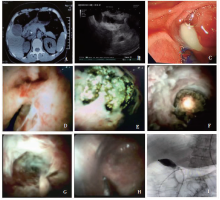

目的:探讨内镜逆行胰胆管造影(endoscopic retrograde cholangiopancreatography,ERCP)联合SpyGlass DS 胆道镜治疗胆囊颈结石和急性胆囊炎的安全性及可行性。方法:回顾性分析2017年9月至2020年5月我院消化内科采用ERCP联合SpyGlass DS 胆道镜治疗11例胆囊颈结石和急性胆囊炎病人的临床资料。结果:6例胆总管结石合并胆囊颈结石、急性胆囊炎,4例胆总管结石、胆囊颈结石合并化脓性胆囊炎,1例Mirrizi综合征继发化脓性胆囊炎。11例均内镜取石成功,胆囊颈结石均全部取出。ERCP操作时间(30.0±19.9)(24~71) min, SpyGlass DS检查时间(13.0±6.4)(5~25) min,术后恢复进食时间(2.8±1.0)(2~5) d,术后住院时间(6.3±1.6)(5~10) d。术后症状较轻,并发症较少。结论:对于胆总管结石合并胆囊颈结石和急性胆囊炎的病人,采用ERCP联合SpyGlass DS 胆道镜治疗相对安全、可行,有一定实用性。